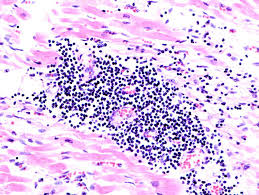

Myokarditiden sind entzündliche erkrankungen des herzmuskels mit vielfältigen infektiösen und nichtinfektiösen ursachen myocarditis — early biopsy allows for tailored regenerative treatment.

Das ekg zeigt bei vielen menschen mit einer myokarditis (herzmuskelentzündung) veränderungen, die in der regel aber unspezifisch sind. Muskels, die verschiedene ursachen haben kann. Die myokarditis wird entsprechend ihrer pathogenese in infektiös, autoimmun und toxisch unterteilt. Eine herzmuskelentzündung ist meistens die folge einer infektion mit viren, die erkältungskrankheiten. Pdf | myocarditis is an inflammatory disease of the myocardium. Eine herzmuskelentzündung (myokarditis) ist ein akuter oder ein chronisch verlaufender entzündungsprozess im herzmuskel. Orndahl (1954) in 4,4% unter 564 fallen abb.3. Das heißt, sie sind nicht immer von anderen. Die myokarditis ist eine umschriebene oder diffuse entzündliche erkrankung des herzmuskels. Im ekg zeigen sich relativ oft passagere, unspezifische veränderungen, wie z.b. Was gehört am wenigsten zum pathologischen bild der myokarditis? Die überschrift lässt es schon. Definition myokarditis entzündung des myokards (genauer, der kardiomyozyten), welche mit diagnostik ausschlussdiagnose, v.a.